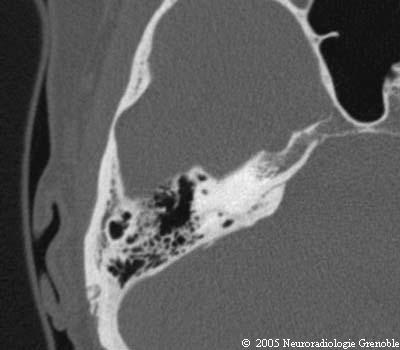

Radioanatomie TDM du rocher normal

Canal semi-circulaire supérieur

Antre